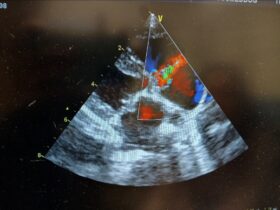

Hello everyone and welcome to my first blog for week 1 of my internship. I headed out to Denver on the 29th to start working on the 30th. On Monday, I got a tour of the building seeing the different departments, cardiology, oncology, surgery, and emergency and critical care. This week, I started in cardiology […]